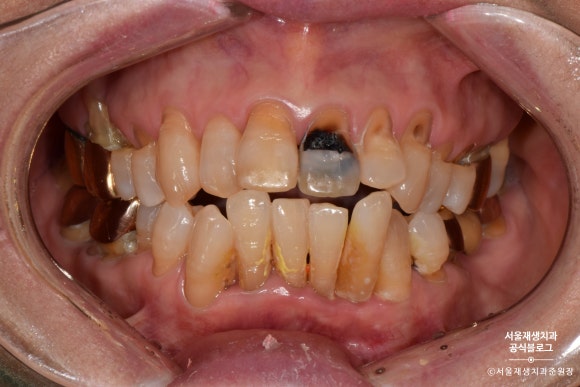

다양한 치경부마모증의 모습들

기본적으로 치아가 미세파절을 동반한 마모를 겪는 현상이기 때문에,

진행된 수준에 따라

접시로 푹 떠낸 것 같은 얕은 마모에서,

도끼로 나무를 찍어낸 듯한 깊은 마모도 존재합니다.

사진으로 만나보실까요?

넓고 완만하게 진행된 치경부마모증의 모습입니다.

도끼로 나무를 찍어낸 듯이 좁고 깊은 케이스도 있습니다.

간혹 패인 부분에 음식이 고이거나

잇솔질이 제대로 되지 않아

충치가 생기기도 합니다.